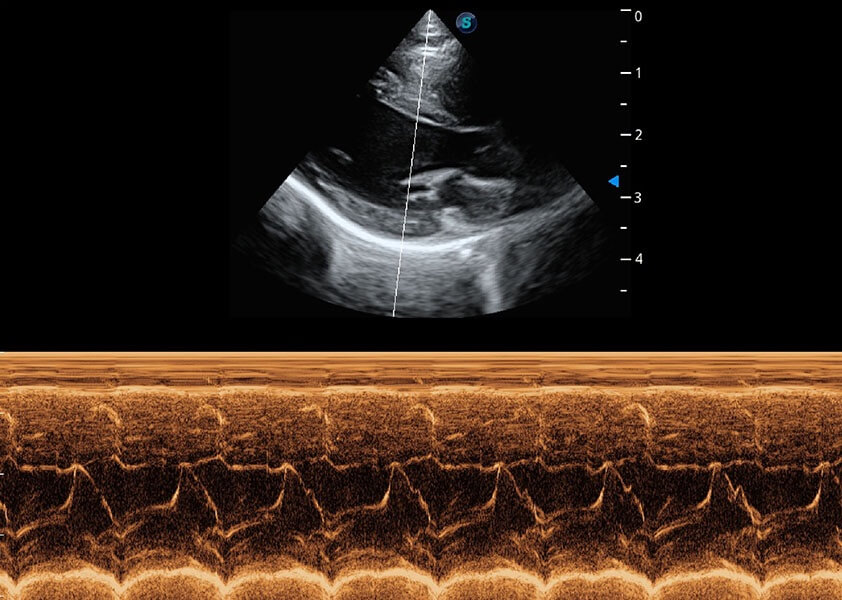

ProPet 60 作为一款高端台式动物超声设备,为动物医生的日常诊断提供了一系列贴合动物临床需求、解决临床实际问题的高级成像功能。凭借全系列高清探头,满足医生对腹部、心脏、生殖、浅表、肌骨等成像的所有需求,切实帮助您提升检查效率,提高诊断信心。

动物是人类最亲密的朋友和最值得信赖的伙伴。狗万官方网站也一直致力于探索动物专用的超声影像解决方案。 全新推出的ProPet系列,是狗万官方网站在动物超声影像智能化、专业化、精准化的一次跨越式革新。动物不能用言语来表述自己的不适,通过超声影像,ProPet系列搭建了动物医生与不同物种沟通的“桥梁”,为动物医生注入了“治愈之力”。